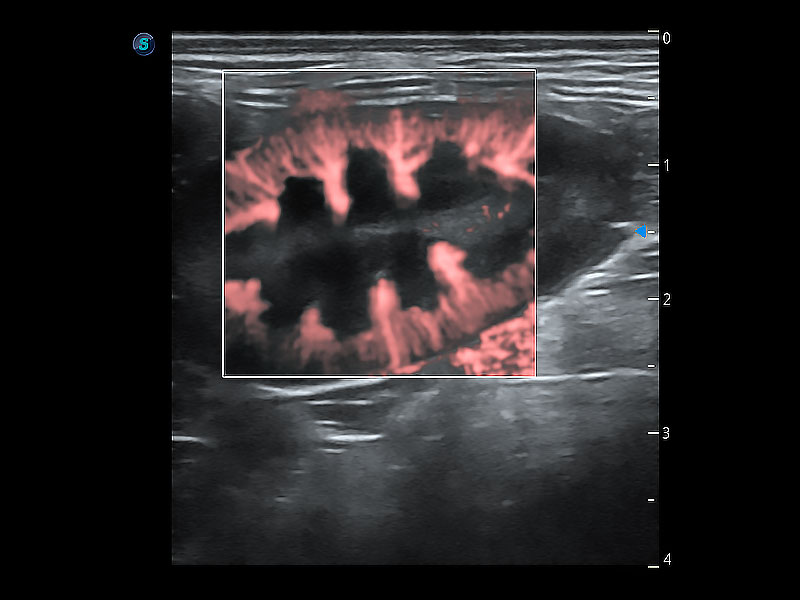

極大提升超低速微細(xì)血流的檢出能力,同時(shí)更精準(zhǔn)地濾除軟組織和超聲信號(hào),為獸用醫(yī)生提供以往無(wú)法通過(guò)常規(guī)血流獲得的疾病診斷信息。

在傳統(tǒng)二維血流成像的基礎(chǔ)上,呈現(xiàn)血流的立體感,具有動(dòng)感的生命力之美。即便是微小的血管也能輕松應(yīng)對(duì),提高了血流的視覺(jué)敏感性。